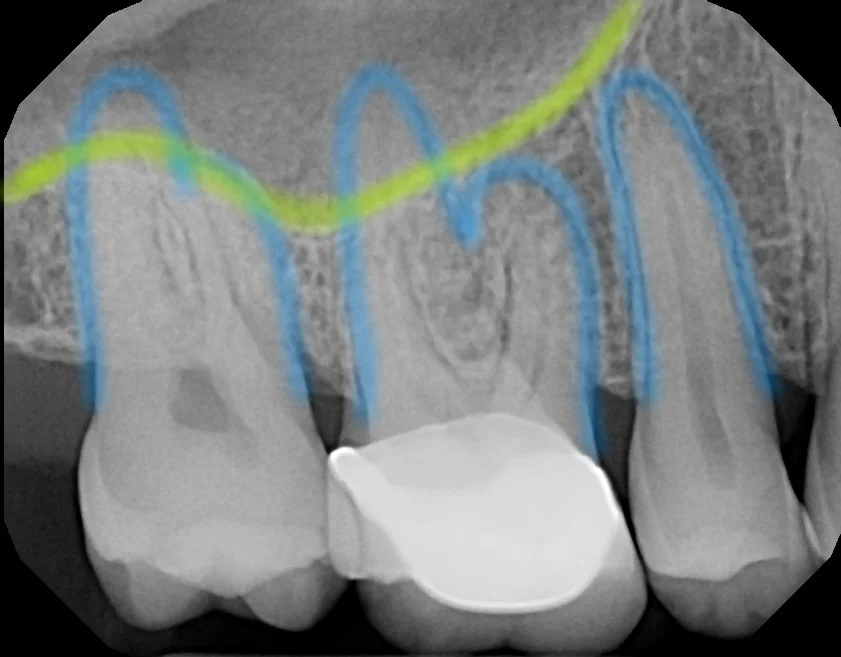

Does Maxillary Sinus Proximity Affect Molar Root Resorption During Distalization Using Invisalign? A CBCT Study

Maxillary sinus & molar roots relationship. Sinus maxillary molar bone radiograph cortical which surrounded